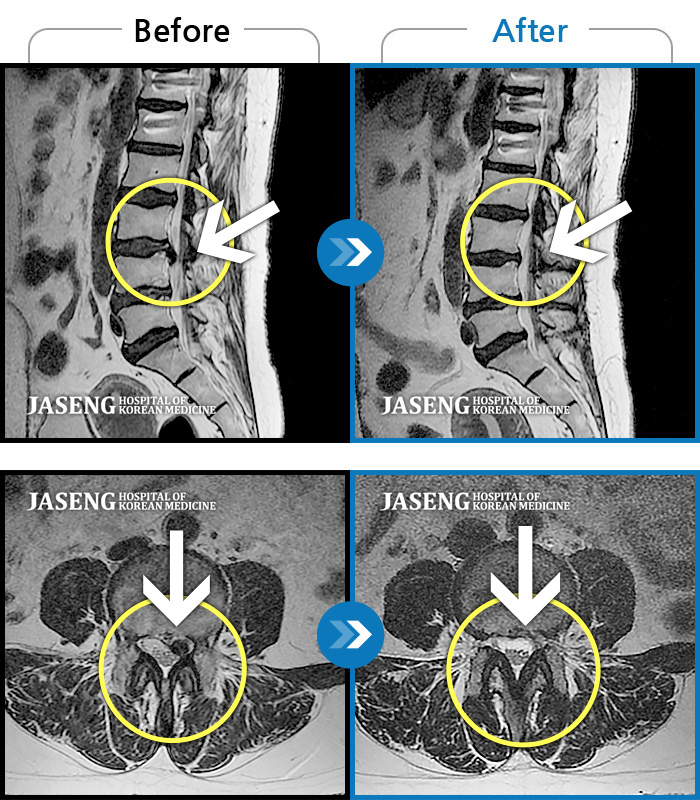

허리디스크

일산 · 김태용 원장

허리 골반통증이 극심했다.

촬영시기

2021.02.06 ~ 0222.01.15

2022.01.17